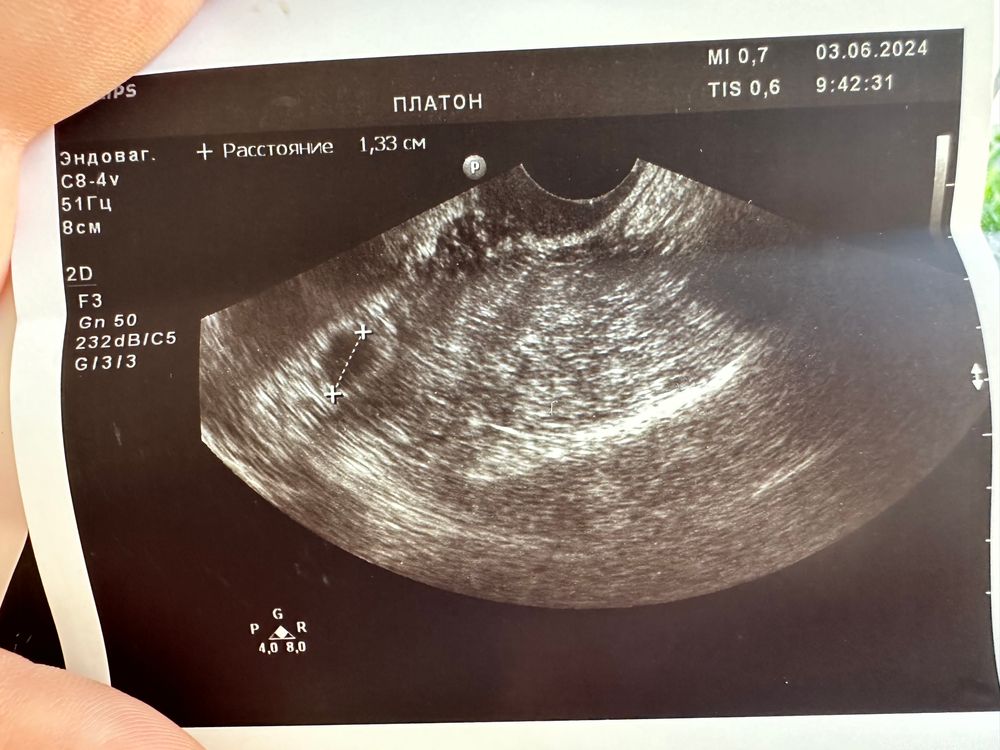

4 эмбриональные недели узи

4 эмбриональные недели узи 148 фотографий